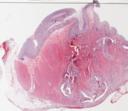

41-01: Eosinophile Colitis (HE)

41-02: Eosinophile Colitis (HE)